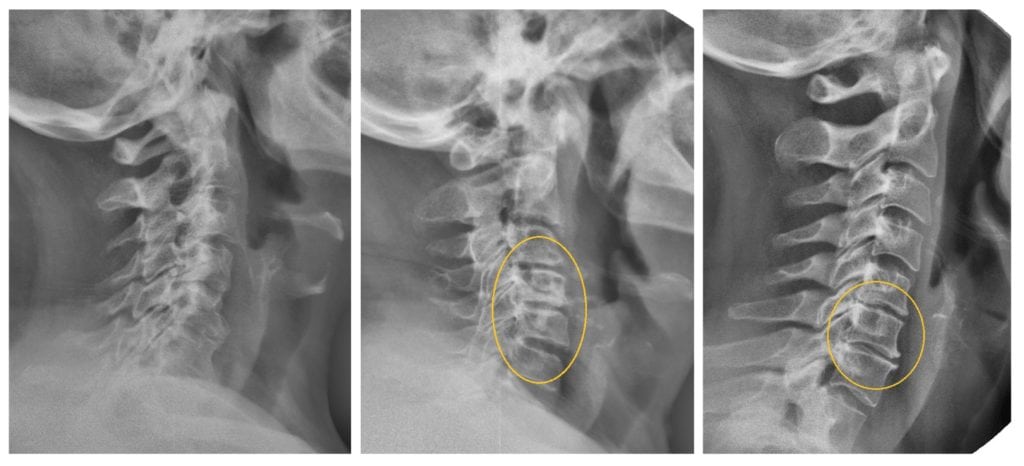

Во время тренировок позвонки могут хрустеть, периодически раздаются щелчки. Происходит то, что недопустимо во время занятий в домашних условиях. Врачам досконально известно анатомическое строение шейного отдела, предварительно они изучают рентгенологические изображения шеи больного. Поэтому хруст и щелчки свидетельствуют только о результативности методики микродвижений.